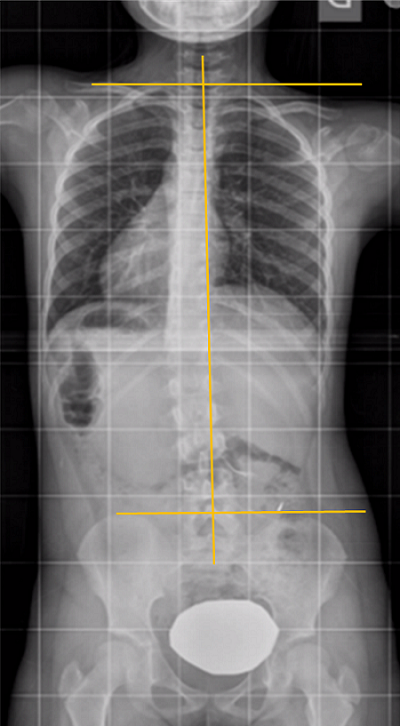

Pero, a veces ocurre que la columna no se ve perfectamente derecha4. ¿Cómo reconocer que se trata de una escoliosis posicional o actitud escoliótica? (Figura 4): los hombros deben estar a la misma altura, porque la articulación del hombro y la pseudoarticulación, escápulo-torácica, se mueven sin influir en la posición de la columna. Ascienden o descienden la clavícula con su movimiento, pero el raquis puede mantenerse perfectamente recto.

Figura 4. Posición inadecuada, actitud escoliótica. Mostrar/ocultar

Una curva larga de toda la columna vertebral dirigida hacia el hombro que se ve más caído indica que el paciente se inclinó armónicamente hacia ese lado (Figura 5). Asimismo, una curva dirigida hacia la pelvis que se eleva, o hacia el miembro que se apoya menos, posiblemente son posicionales.

Figura 5. Escoliosis posicional. Inclinación del hombro hacia el lado más bajo. La columna vertebral se curva hacia el hombro que se ve más caído, indica que el paciente se inclinó armónicamente hacia ese lado. Mostrar/ocultar

En las dismetrías, el paciente caerá hacia el lado más bajo, como mencionamos sobre la Figura 5, pero para compensar este desequilibrio la columna puede inclinarse hacia el lado más alto, bajando el hombro de ese lado. Estas curvas son lógicas y no son escoliosis. Sin embargo, podemos encontrarnos con situaciones contradictorias o mixtas (Figura 6).

Figura 6. Escoliosis posicional. Dismetría de miembros inferiores: la columna vertebral se inclina hacia el lado más alto y además eleva el hombro del mismo lado. Es una situación mecánicamente ilógica, debida a posiciones que adoptan los pacientes en el momento de hacer la radiografía. . Mostrar/ocultar